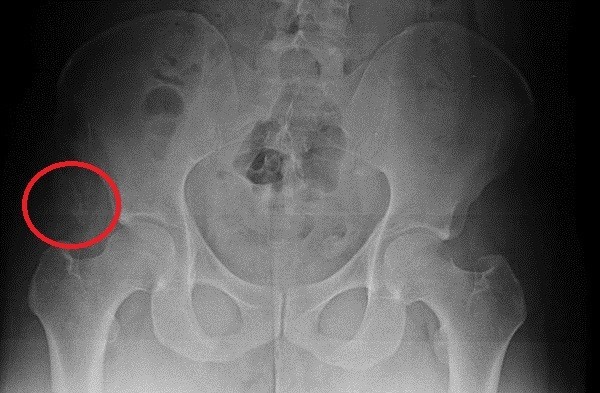

박주신씨의 엑스레이를 보면 ‘견열 골절’(牽裂骨折)이 보인다.

‘견열 골절’은 쉽게 말해 인대와 뼈가 완전히 성숙되지 않은 청소년기에, 무리한 힘이 작용했거나 충격을 받았을 때, 인대가 뼈를 잡아당기면서 찢어지는 부상이다.

이런 상처는 만들려 해도 할 수가 없다. 그런데 박주신씨의 고등학교 기록을 보면 등산이나 국토대장정 등 육체적 강도가 있는 활동을 한 것으로 나온다.

이런 부상을 당한 상태에서, 등산이나 국토대장정 같은 활동을 했다는 건 납득하기 쉽지 않다.

- ▲ ▲자생한방병원과 명지병원에서 촬영한 박주신 엑스레이 영상자료. 오른쪽 골반에 견열골절이 보인다. ⓒ 뉴데일리DB

▲ 박주신씨의 골반 부위 X-Ray 사진.ⓒ 뉴데일리DB

“오른쪽 엉덩이 쪽에서 골절된 뼈 조각을 찾았다.

저는 매일 같이 뼈만 보는 사람이다.

사진을 들여다보고 있으면 어느 정도의 정황을 유추할 수 있다.엑스레이를 보면 청소년기에 근육이 붙는 자리 쪽 오른쪽 골반 뼈에, 견열골절(인대가 손상되면서 뼈조각이 떨어져 나간 것)이 왔다.

이 엑스레이의 주인이 아주 험하게 살았다고 단정하는 이유다.”